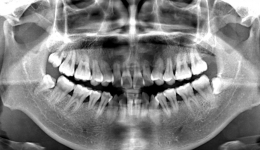

• “聪明可靠”的口腔全景CT来喽!赶紧上车来“瞧瞧”~

“聪明可靠”的口腔全景CT来喽!赶紧上车来“瞧瞧”~

日常生活中,不少朋友都有过拍“牙片”的体验。在口腔科,医生进行完初步检查后,都会根据治疗需要给患者安排“拍片”。上全新设备德国卡瓦X-TREND口腔全景CT该设备拥有领面自锁、颌面聚焦及颌面独立头影技术,并且在抗金属伪影方面拥有卓越...